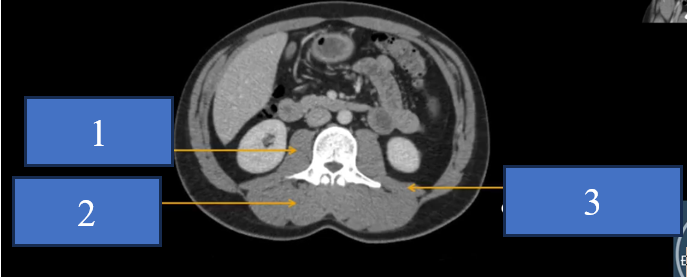

cq trong hình ?